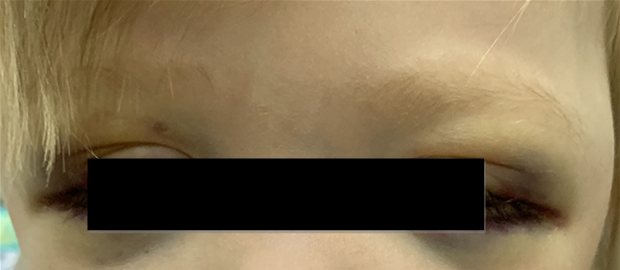

Локализация опухоли в шейно-грудном отделе симпатического отдела позвоночника вызывает синдром Горнера (сужение зрачка, разные размеры зрачков, покраснение и/или опущение верхнего века и небольшое поднятие нижнего). Другими изменениями в области глаз могут быть кровоизлияния в кожу или слизистую оболочку, «синяки» на веках и под глазами. На поздней стадии болезни иногда появляются черные круги вокруг глаз (гематома в виде очков) (рис. 3).

Рис. 3.1. Симптом «очков»

Рис. 3.2. Симптом «очков» при метастазах в орбиту